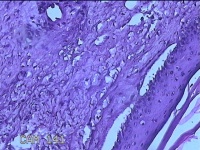

右膝部皮肤肉芽肿

性别

男

年龄

13岁

临床诊断

皮肤肉芽肿

一般病史

外伤后,出现右膝部皮肤肉芽肿形成。

标本名称

大体所见

灰白暗红色带皮肤样组织2.8x1.8x1.3cm,表面糜烂,切面灰白粉红色,质软。

图3